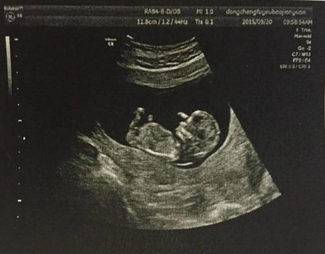

以灰阶即亮度(brightness)模式形式来诊断疾病称“二维显示”,因亮度第一个英文字母是B,故称B超,又称二维超声或灰阶超声。

B型超声检查的范围很广,不同的检查部位,检查前的准备亦不相同。①腹部检查:包括肝、胆、胰、脾及腹腔等。一般应该空腹检查,因为进食后,胃及肠道产生气体,影响超声的穿透,空腹检查效果最好。②妇科检查:应该饮水憋尿,当膀胱充盈后,挤开肠管,让超声更好的穿透到盆腔,清晰的显示子宫及卵巢的正常与异常。③泌尿系检查:应该多饮水,当膀胱充盈后,内部的结石、肿瘤、息肉等,即能更好的显示。④体表肿物及病变:可以即时检查,一般无需特殊准备。⑤心脏及四肢血管检查,亦无需准备。

B型超声是医学影像学超声的主要检查方法,虽然超声的发展突飞猛进,如内镜超声、超声造影、三维成像、弹性成像等等,都是在B型超声基础上发展起来的。因此,凡是进行超声工作的医师及被检查的患者,都应该了解B型超声的临床医学特点、检查前准备、检查范围及注意事项等等,以便更好地应用它来为被检查者服务服务。